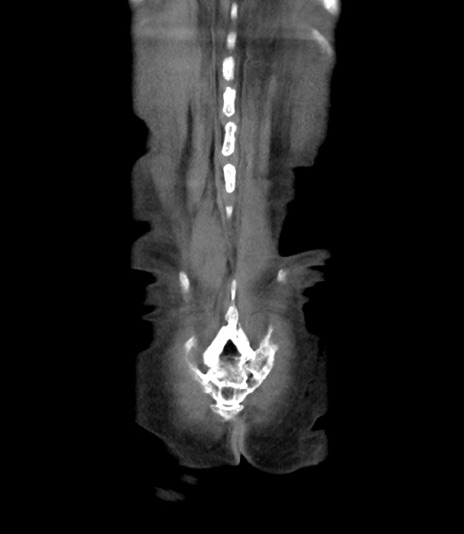

矢状断像

【症例】 70歳代男性

【主訴】右鼠径部腫瘤、疼痛

【現病歴】本日朝より上記主訴あり、受診。

【既往歴】膀胱癌にて膀胱全摘、両側尿管皮膚瘻

【データ】WBC 5600、CRP 0.56